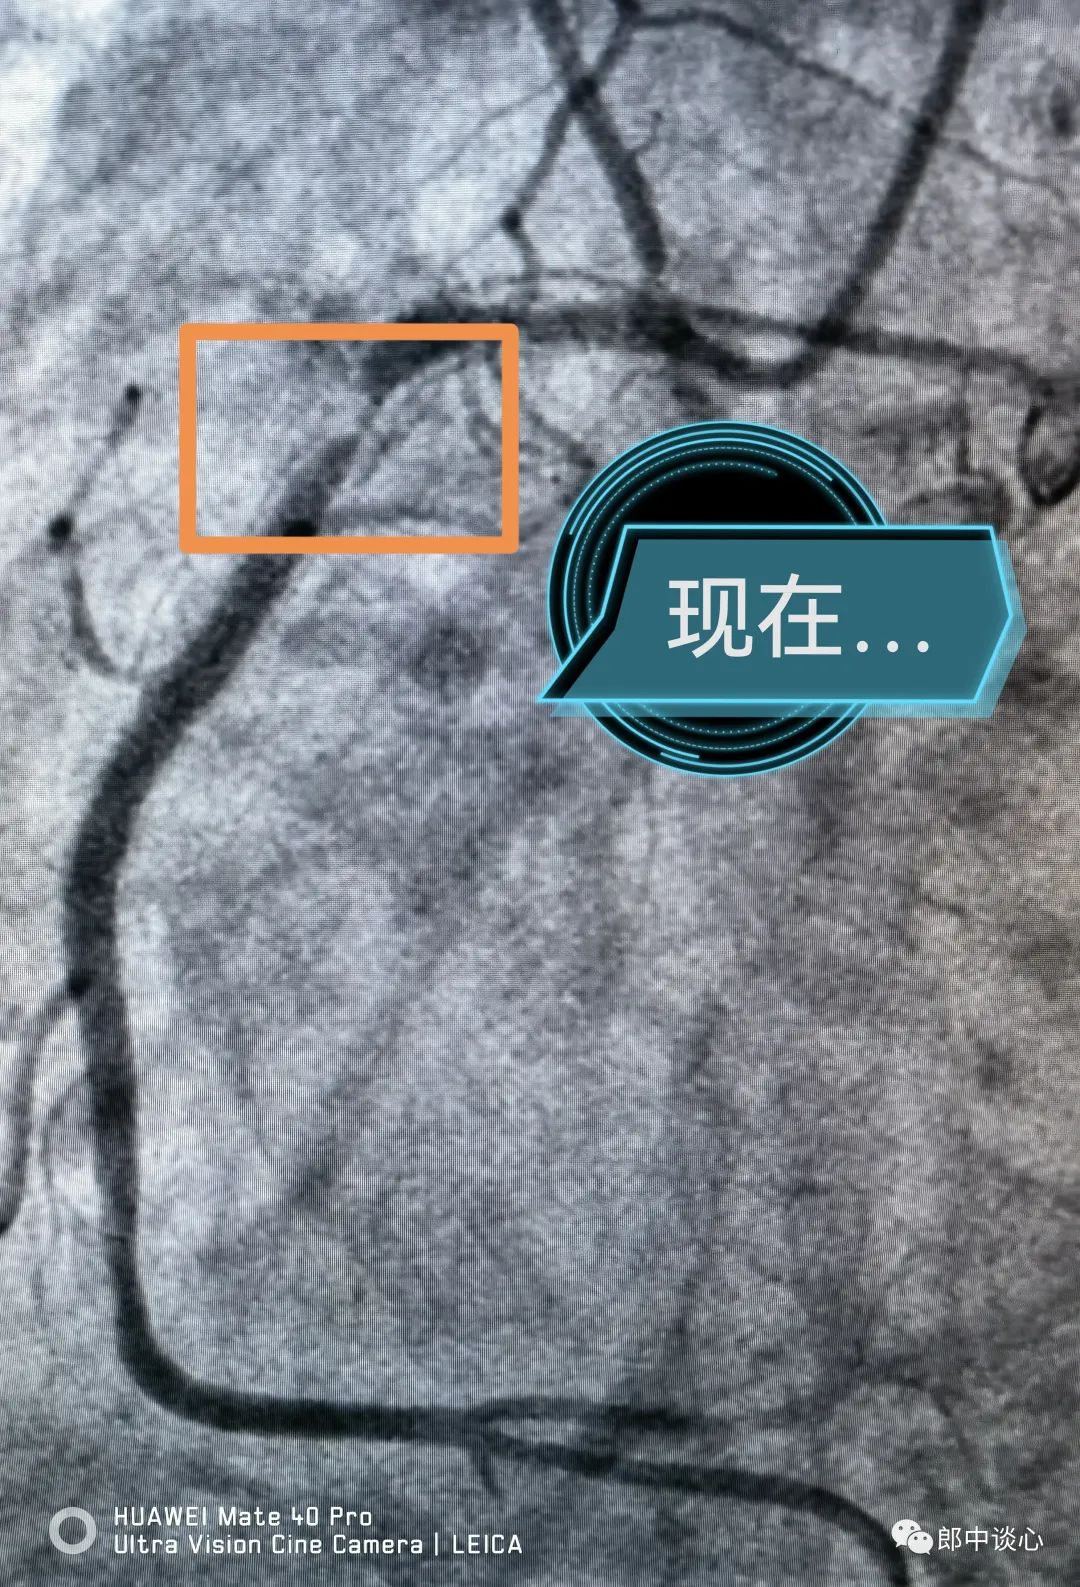

冠脉造影,果然前降支完全闭塞了!回旋支也是重度狭窄且是不稳定病变!(黄框内为病变段)